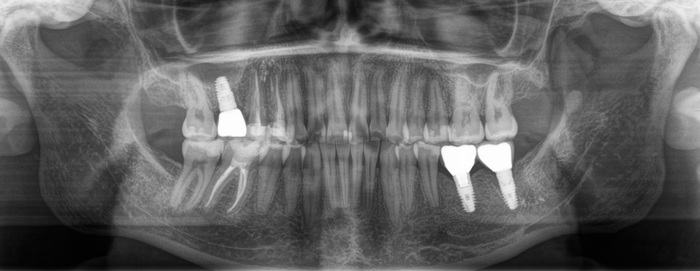

Прикус:

За эти годы ситуация усугубилась, стираемость зубов прогрессировала.

Вот как выглядели зубы в 2018 году:

А это через каких-то 3 года, 2021:

Обратите внимание, как сильно стерлась верхняя «двойка» и нижний клык:

Ниже ситуация от июня 2023:

Есть такое понятие, как клыковое ведение (или клыковая дезокклюзия) – это разобщение задних зубов во время боковых движений нижней челюсти. Иными словами, (прочтите медленно) при смещении нижней челюсти в сторону, двигаясь клыком нижней челюсти по клыку верхней челюсти на момент контакта бугров, у боковых зубов не должно быть контакта. В данном случае он есть именно на 7ках:

Оранжевым цветом отмечена стираемость зубов, а красным место контакта.

Зубы стерлись, высота прикуса занизилась. В связи с чем появился преждевременный контакт керамической коронки на нижнем 7м зубе (керамика не стирается) и верхним 7м зубом.

Поэтому, из-за постоянной перегрузки винт и сломался. Могучий Иван снова достал винт, заменил его на новый и прикрутил обратно ту же самую коронку. Подточил 7й зуб, вывив его из преждевременного контакта с нижним. (снимки сделаны при помощи зеркала) на 3,4,5,6 зубах отпечатана копирка, на 7м нет: